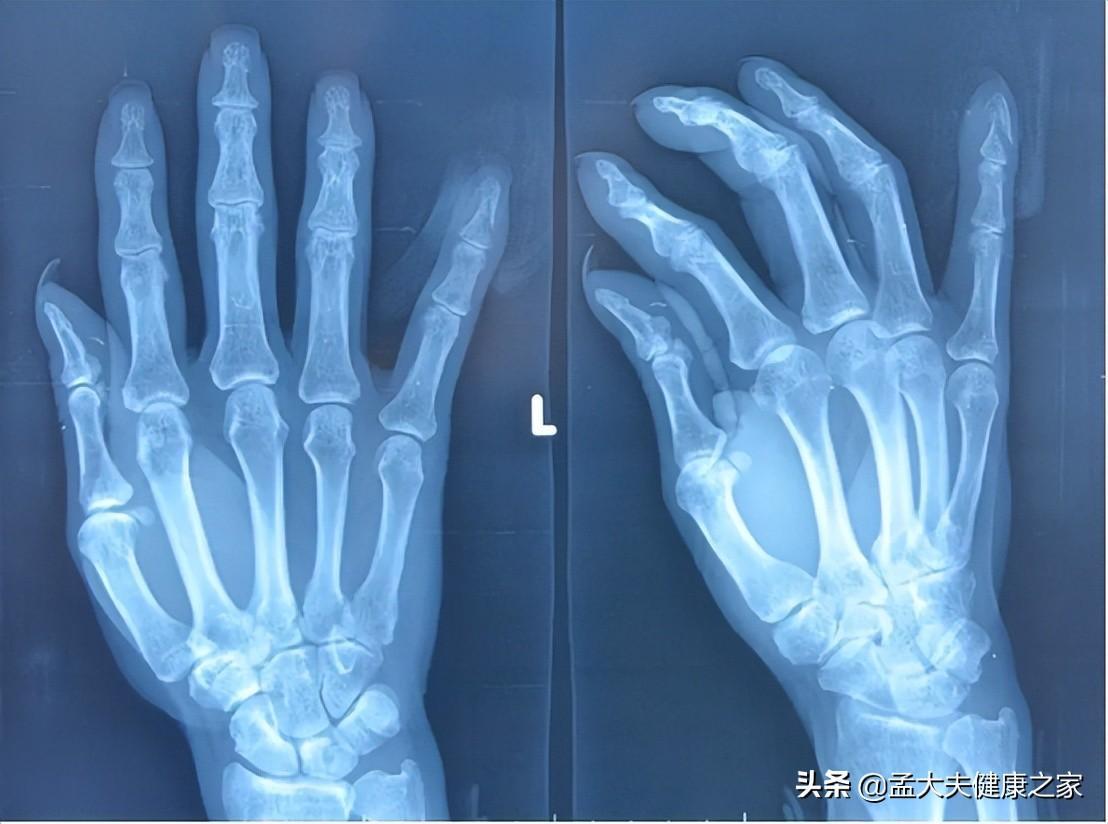

在实验中,唐纳德选择每天掰响自己的左手,右手则作为对照。在历经60年后对双手进行检查,发现两只手没有任何差异产生,并且都没有产生关节炎。这成为了扳倒掰手指导致关节炎说法的有力证据。